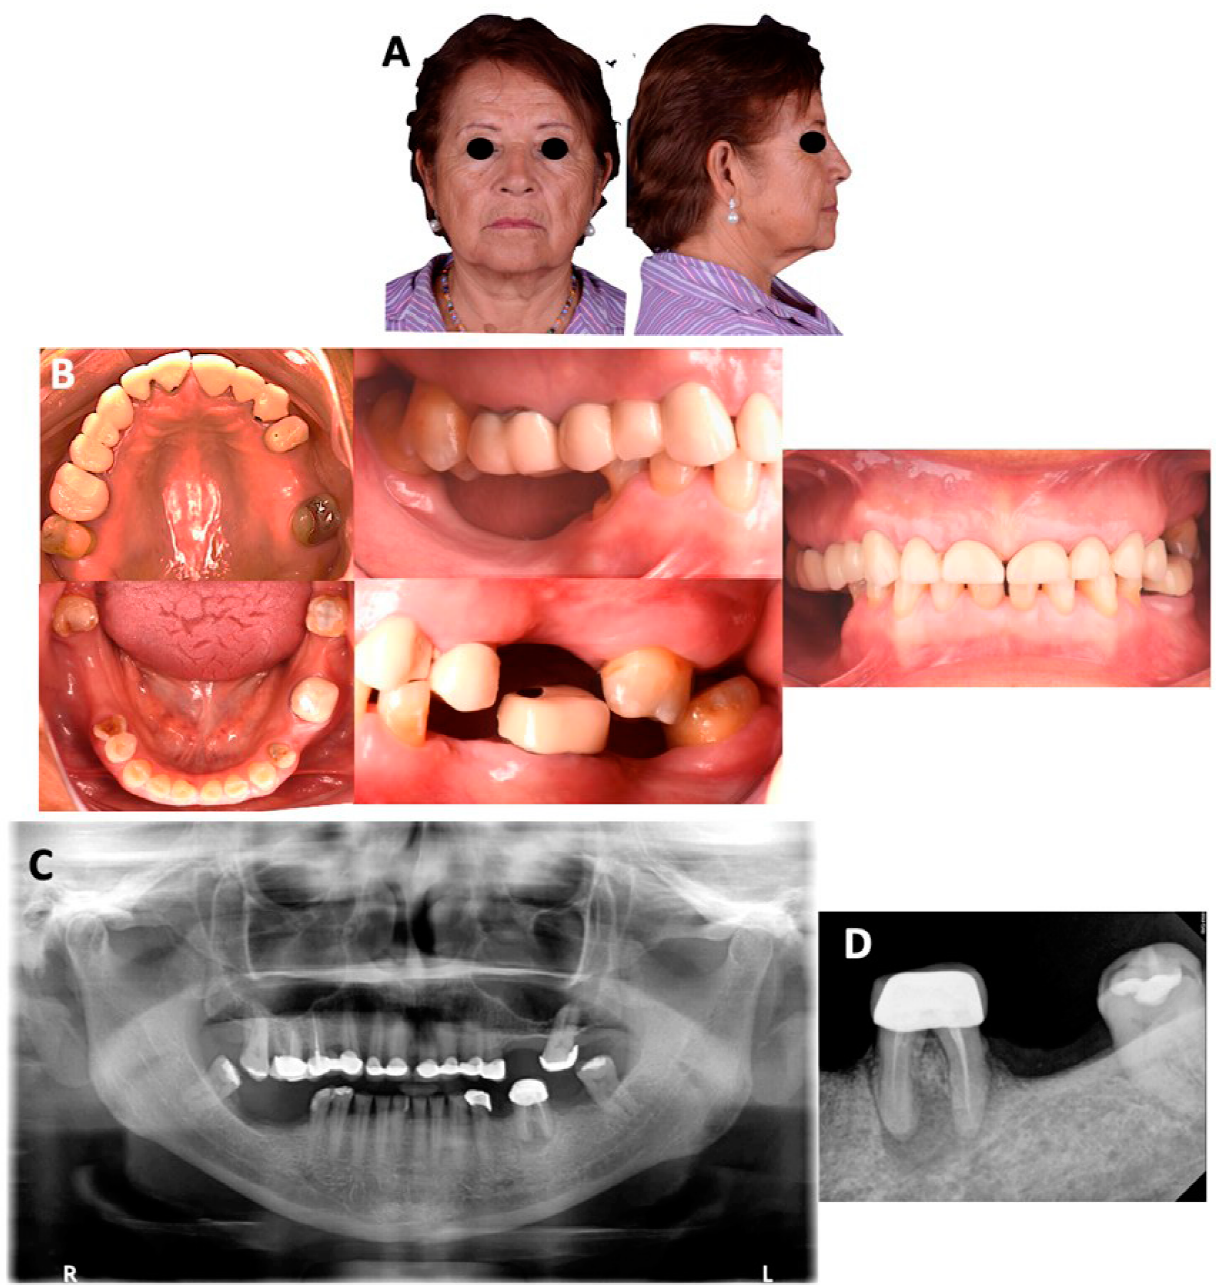

Se presenta paciente femenino de 62 años, cuyo motivo de consulta fue: “tengo mis dientes muy pequeños y no puedo comer a gusto”. La paciente presentó un biotipo facial mesocefálico con perfil recto, tercios faciales simétricos, la línea interpupilar coincide con la línea intercomisural, frente recta, proyección del puente nasal recto, buena proyección del tercio medio, labios delgados, sonrisa baja, no mostró corredores bucales, los bordes incisales no coincidieron con la línea de la sonrisa y no mostró encía en sonrisa máxima. (Figura 1. A). En la Tabla 1 se muestran las medidas del análisis facial de acuerdo con Fradeani12. En el análisis intraoral, la paciente presentó arcos ovoides en ambas arcadas, al igual que ausencia de los dientes 18, 14, 25, 26, 28, 35 y 37, tratamientos de conductos de los dientes 16 y 15, coronas de metal-porcelana en los dientes 15, 13, 11, 12, 21, 22, 23, 24, 25, 26 y 28, restauraciones desajustadas en los dientes 27 y 38. Además presentó atrición generalizada (Figura 1. B). En la ortopantomografía se observaron los cóndilos aparentemente sanos, vías aéreas ligeramente obstruidas y senos maxilares neumatizados (Figura 1. C). En el estudio radiográfico dentoalveolar tanto de los sextantes superiores como de los inferiores mostraron todos los dientes con buen soporte óseo, continuidad de la lámina dura y tejidos periapicales normales a excepción del diente 36, donde se observó pérdida ósea y una zona radiolúcida en el ápice (Figura 1. D).

Figura 1 Fotografías extraorales, intraorales y radiografías iniciales. A. Fotografía de frente y lateral derecha. B. Fotografías intraorales iniciales (oclusal superior e inferior, frontal y laterales). C. Ortopantomografía. D. Radiografía dentoalveolar del diente 36.